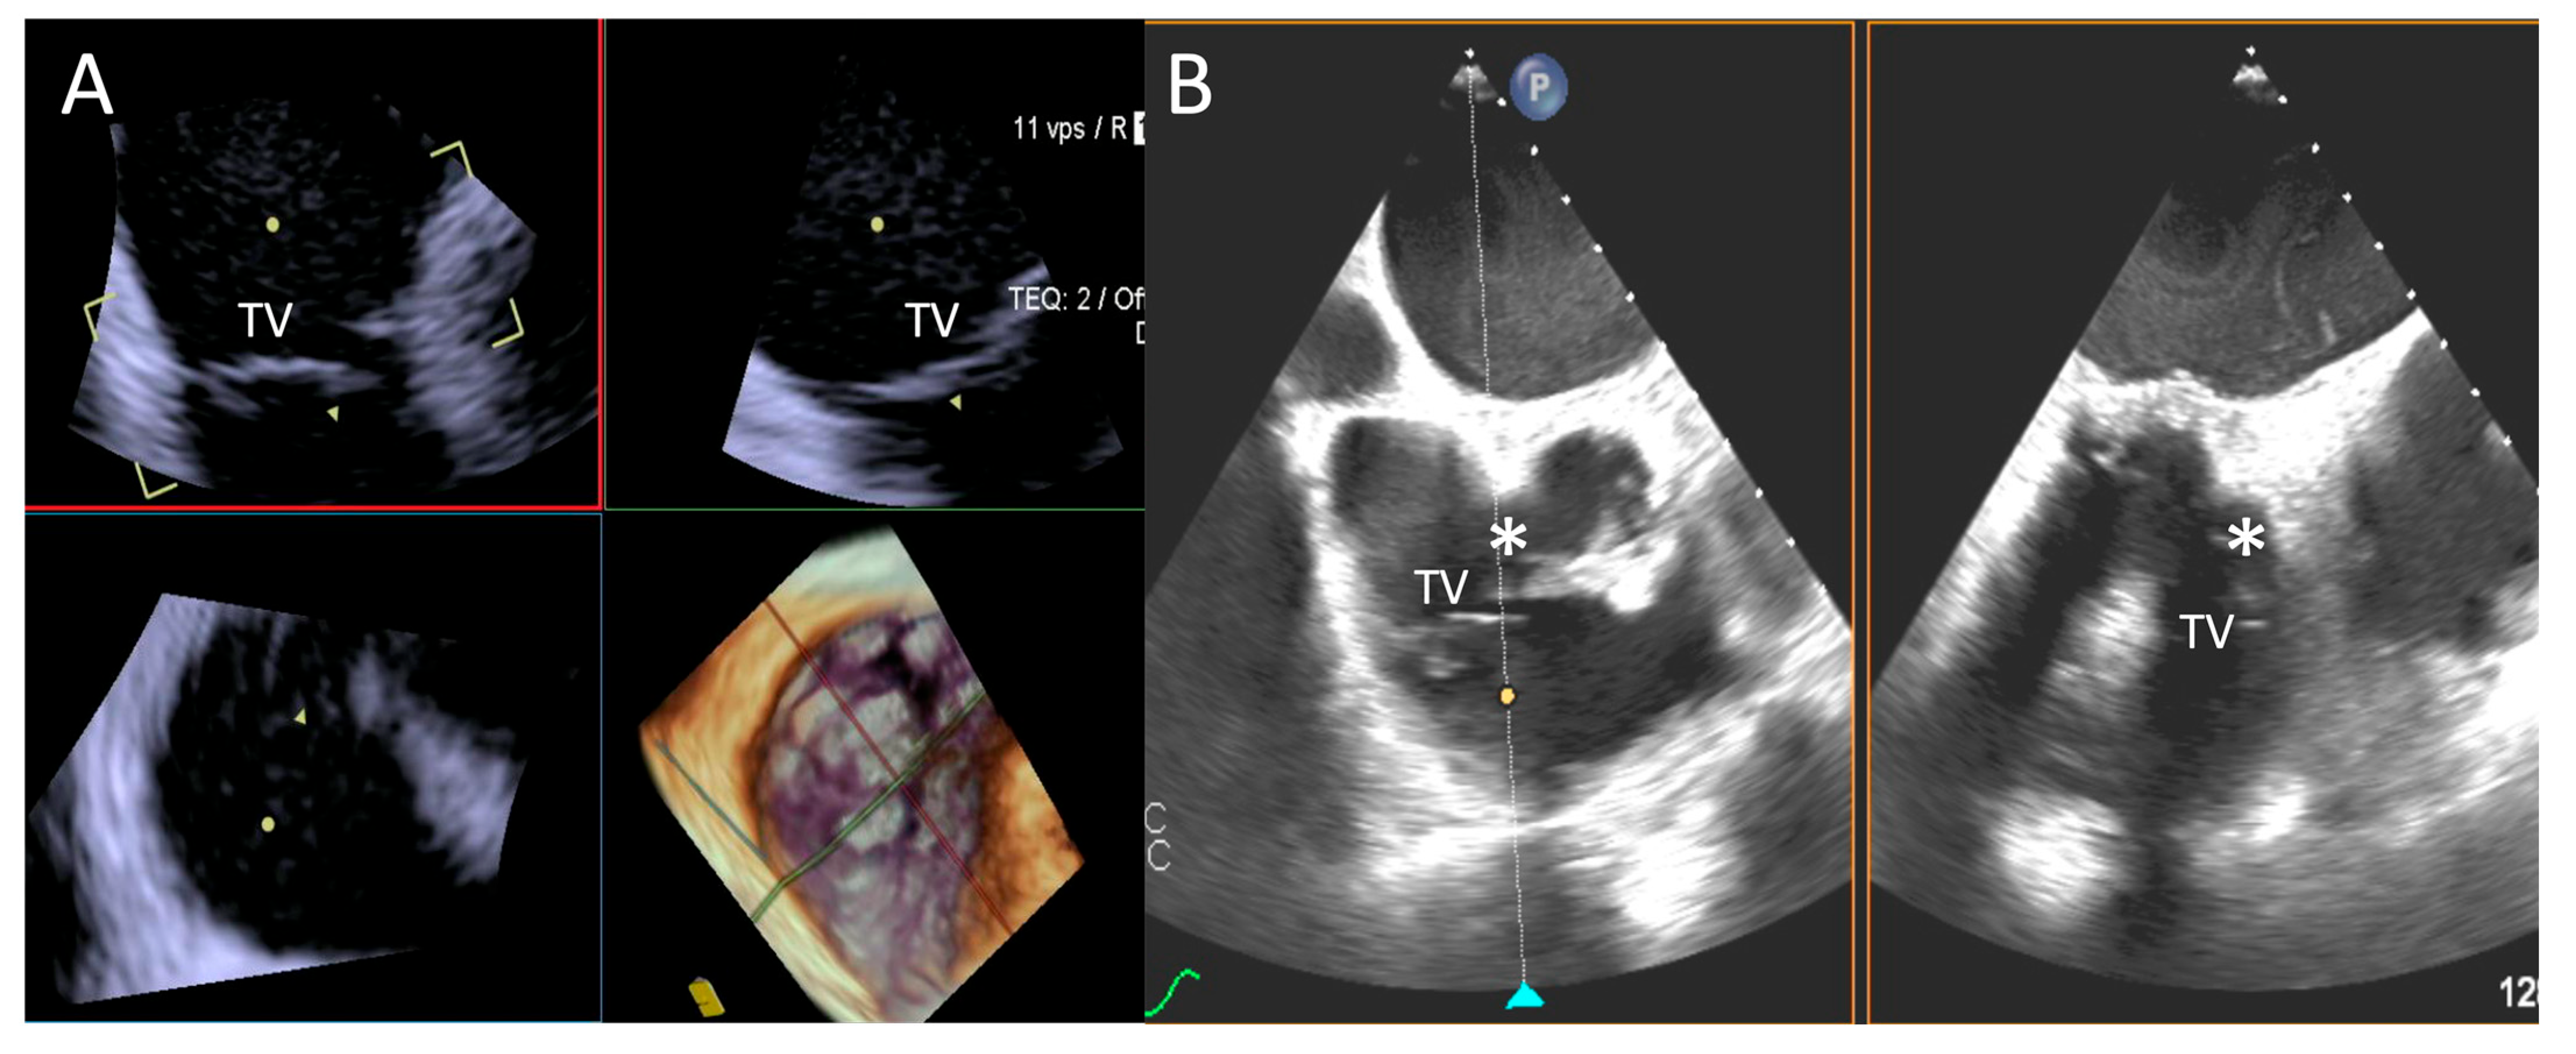

- Step number 3: steering and valve approach.

- -

- Step number 4: ensuring perpendicularity and correct trajectory.